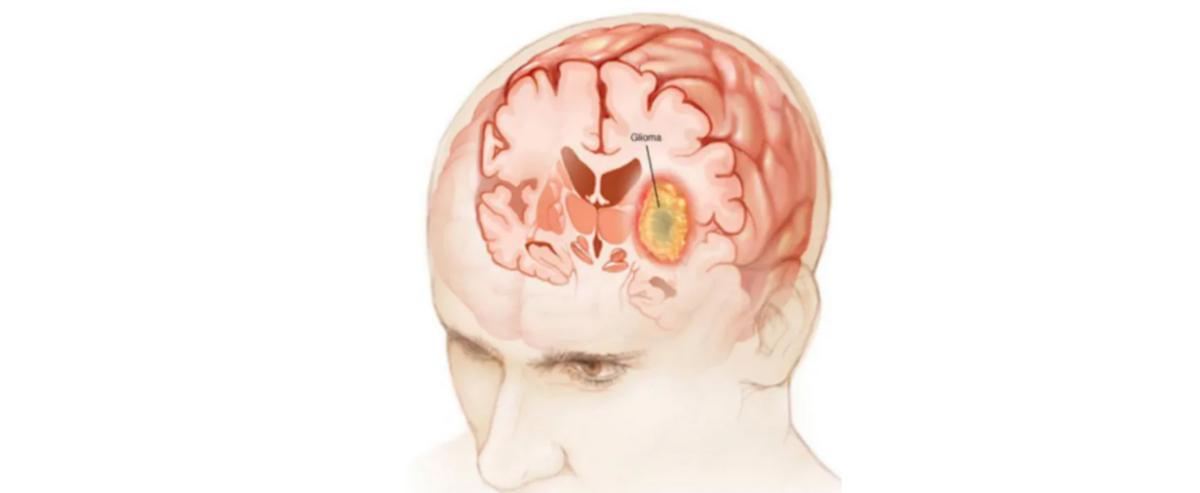

1. Gliomas

Gliomas are the most common type of brain tumor, accounting for 80% of primary intracranial malignant tumors.

Gliomas can be classified into grades I–IV, with grades I and II being low-grade gliomas, and grades III and IV being high-grade gliomas.

Gliomas can also be subdivided into specific pathological types, such as grade I subependymoma; grade II astrocytoma and oligodendroglial tumors; grade III anaplastic astrocytoma and anaplastic oligodendroglial tumors; and grade IV glioblastoma, among others.

As the grade increases, the malignancy of the tumor progressively rises.